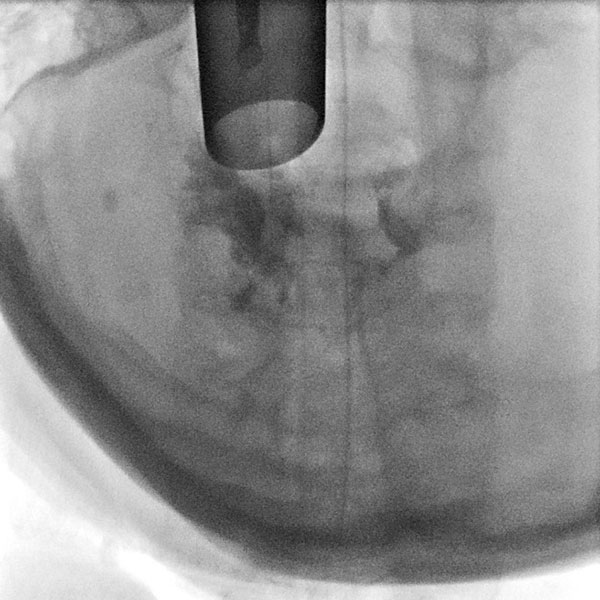

Thus it was decided to sclerose the portions of the venous malformation directly obstructing the airway in the area of the larynx. In biplanar angiography, the rigid laryngoscope is first used to visualize the situation (left image). In the endolarynx, the vocal cords are completely obscured by supraglottic parts of the venous malformation and are no longer visible.

For sclerotherapy, a butterfly needle is advanced through the rigid laryngoscope using grasping forceps into the venous malformation for direct puncture. After aspiration of blood, contrast medium is injected to prove needle placement in the venous malformation before injection of the sclerosing agent.

Control fluoroscopy after contrast injection shows correct needle placement in the venous malformation without outflow via a major communicating vein. The venous malformation can thus be well sclerosed via this position.